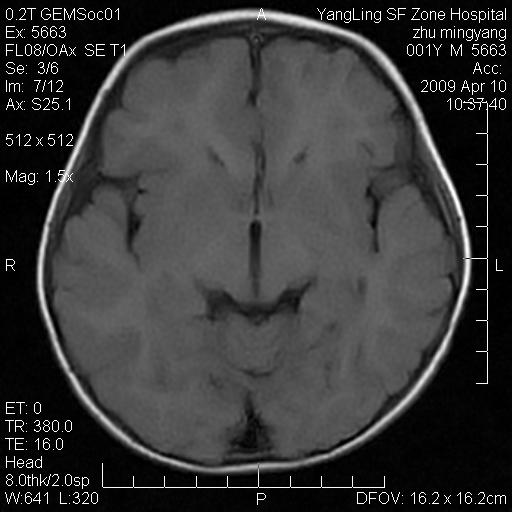

患者:1岁半,两天前外伤收住我院,ct检查小脑占位

考虑星形细胞瘤,建议增强

髓母细胞瘤或血管母细胞瘤,增强后可以鉴别;影像资料见 <。鱼博浪老师的《中枢神经系统ct与mr鉴别诊断》 小脑部肿瘤章节。

髓母细胞瘤或血管母细胞瘤!支持!

支持考虑髓母细胞瘤

考虑----髓母细胞瘤可能性大

考虑髓母细胞瘤或室管膜瘤。

支持髓母细胞瘤。

考虑髓母细胞瘤。

考虑髓母细胞瘤或星形细胞瘤

考虑髓母细胞瘤.

考虑髓母细胞瘤可能性大。

小脑肿瘤.考虑髓母细胞瘤可能.

就病灶部位及临床资料首先考虑髓母.